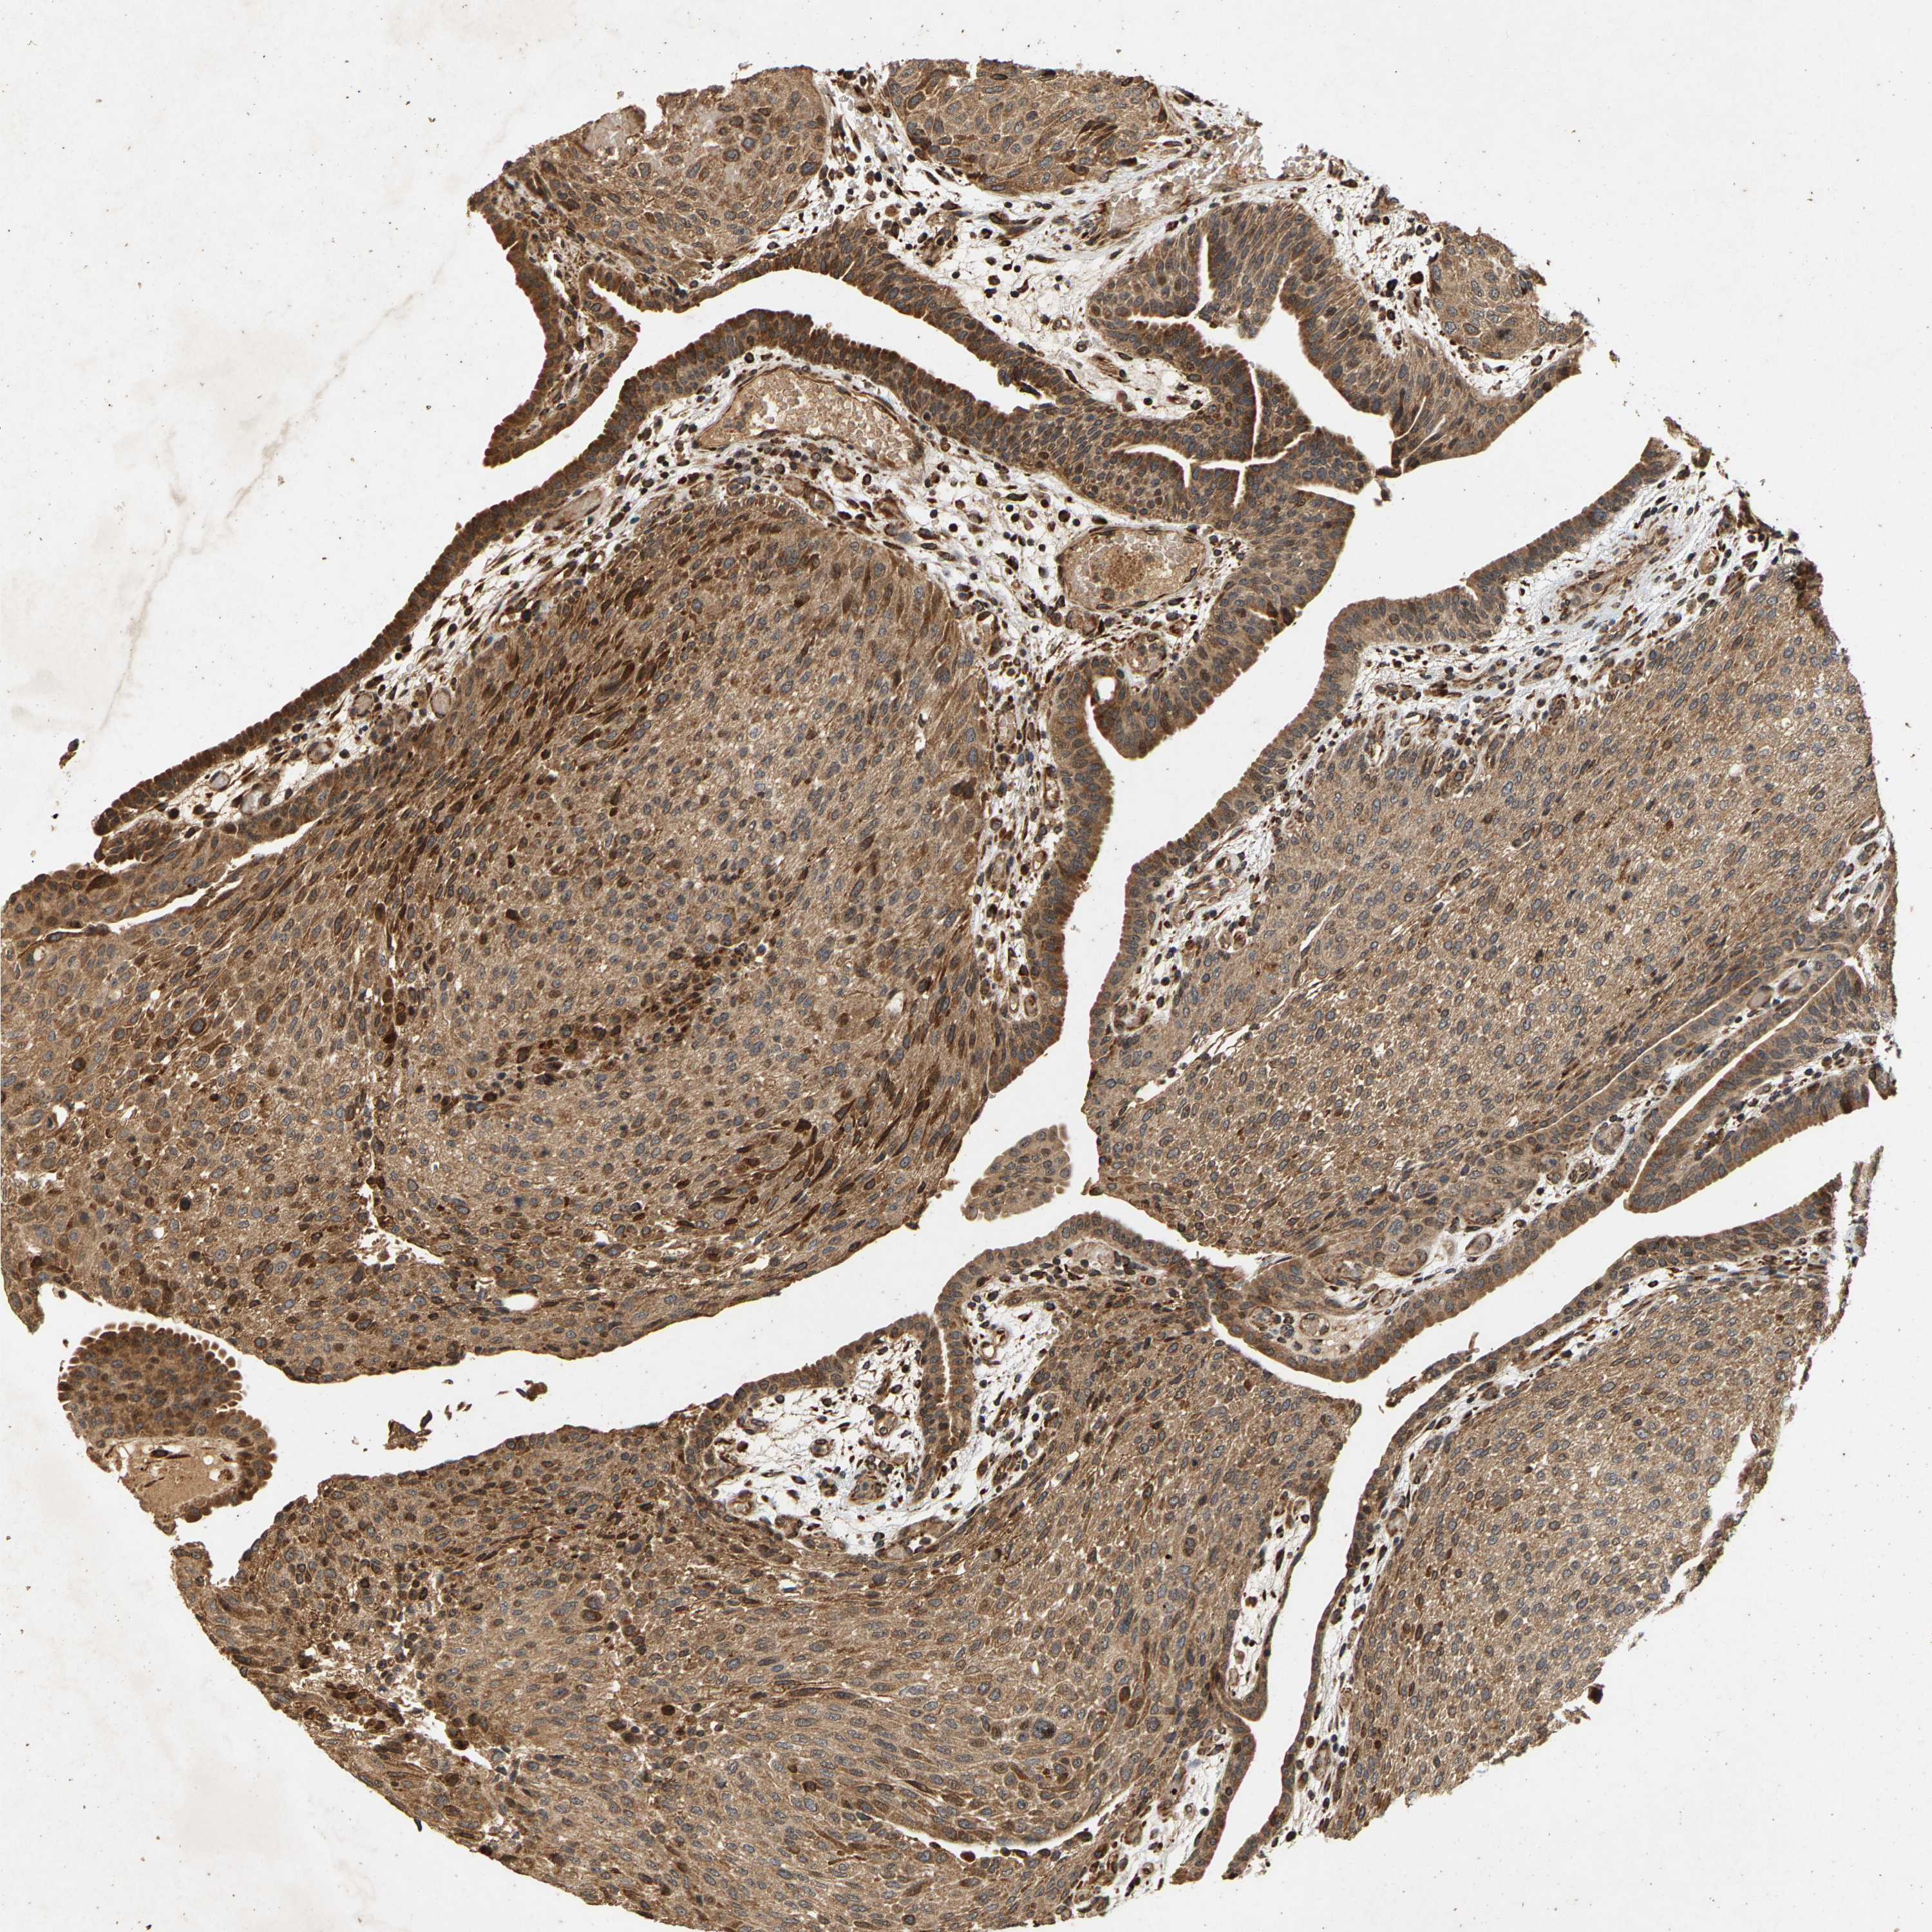

UROTHELIAL CANCER - Protein expressioni

A mouse-over function shows sample information and annotation data. Click on an image to view it in a full screen mode. Samples can be filtered based on level of antibody staining by selecting one or several of the following categories: high, medium, low and not detected. The assay and annotation is described here.

Antibody stainingi

Antibody staining in the annotated cell types in the current human tissue is reported as not detected, low, medium, or high, based on conventional immunohistochemistry profiling in selected tissues. This score is based on the combination of the staining intensity and fraction of stained cells.

Each image is clickable and will lead to virtual microscopy that enables deeper exploration of all samples and also displays staining intensity scores, fraction scores and subcellular localization as well as patient and tissue information for each sample.

Antibody HPA018837

Antibody HPA020553

Staining

High

Medium

Low

Not detected

Intensity

Strong

Moderate

Weak

Negative

Quantity

>75%

75%-25%

<25%

None

Location

Nuclear

Cytoplasmic/membranous

Cytoplasmic/membranous,nuclear

Urothelial carcinoma, High grade